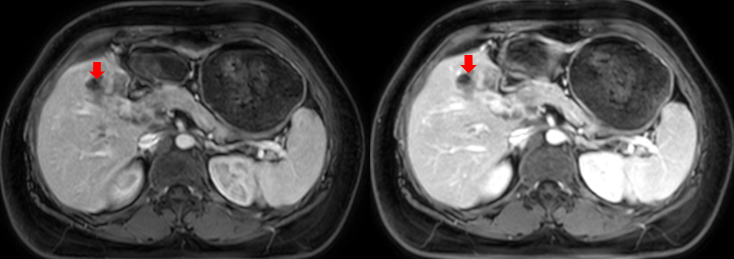

Hình 4: Cộng hưởng từ ổ bụng: Hình ảnh nhu mô gan có các nốt, lớn nhất kích thước 26x17mm, sau tiêm ngấm thuốc dạng viền ( mũi tên đỏ).